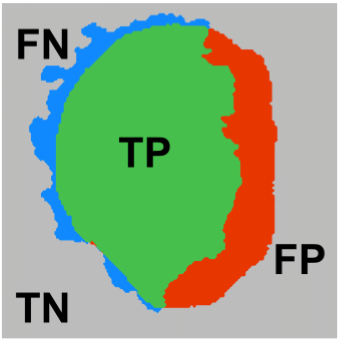

Matthews Correlation Coefficient Loss for Deep Convolutional Networks: Application to Skin Lesion Segmentation

Kumar Abhishek, Ghassan Hamarneh

International Symposium on Biomedical Imaging (ISBI), 2021 We propose a new overlap-based loss function for binary segmentation that takes into account the true negative pixels and achieves a better sensitivity-specificity trade-off than the popular Dice loss. [Abstract] [BibTeX] [Poster]

The segmentation of skin lesions is a crucial task in clinical decision support systems for the computer aided diagnosis of skin lesions. Although deep learning-based approaches have improved segmentation performance, these models are often susceptible to class imbalance in the data, particularly, the fraction of the image occupied by the background healthy skin. Despite variations of the popular Dice loss function being proposed to tackle the class imbalance problem, the Dice loss formulation does not penalize misclassifications of the background pixels. We propose a novel metric-based loss function using the Matthews correlation coefficient, a metric that has been shown to be efficient in scenarios with skewed class distributions, and use it to optimize deep segmentation models. Evaluations on three skin lesion image datasets: the ISBI ISIC 2017 Skin Lesion Segmentation Challenge dataset, the DermoFit Image Library, and the PH2 dataset, show that models trained using the proposed loss function outperform those trained using Dice loss by 11.25%, 4.87%, and 0.76% respectively in the mean Jaccard index. The code is available on GitHub.